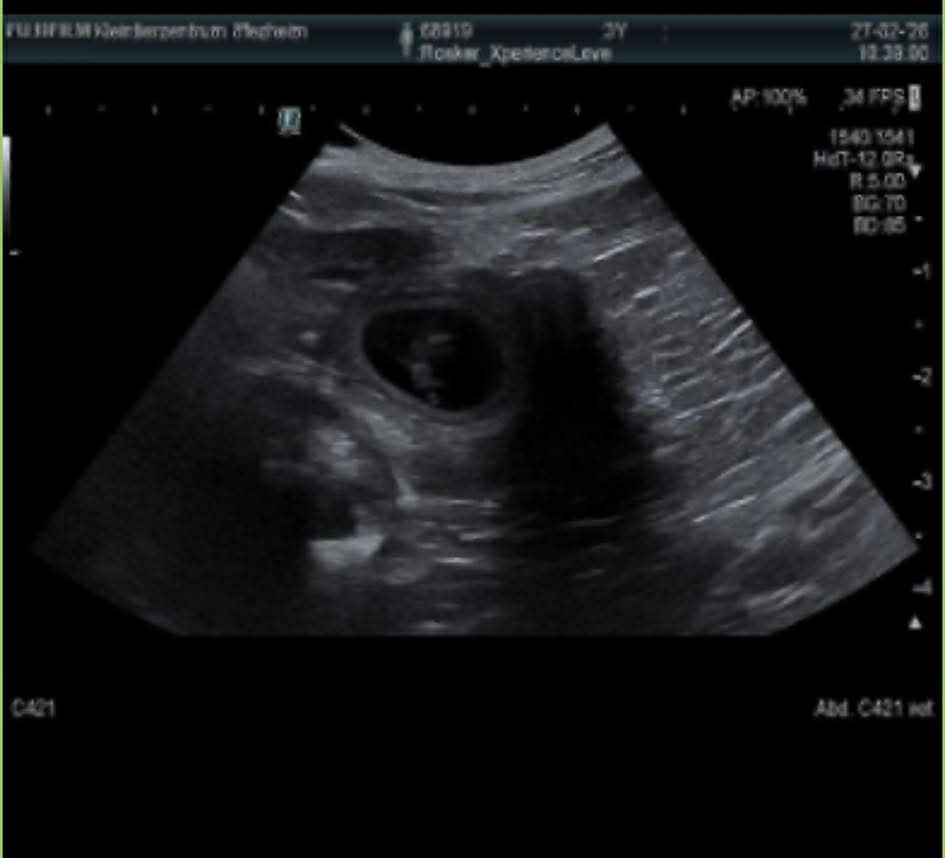

4. März 2026KommentarnavigationZurückVorheriger Beitrag:Vivi wurde am 5.2 von Jake (Plainfire‘s I‘m On Fire) gedeckt.Ähnliche BeiträgeVivi wurde am 5.2 von Jake (Plainfire‘s I‘m On Fire) gedeckt.9. Februar 2026Vivi ist läufig und soll Anfang Februar gedeckt werden26. Januar 2026Das Jahr 2026 fängt gut an. Wir gratulieren Zorro zum Titel „Deutscher Champion (VDH)“7. Januar 2026